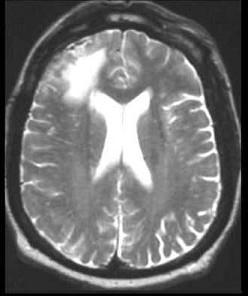

问题 男,16岁,发热、头痛半月,抽搐、意识模糊一天,CT检查如图,最可能的诊断为()

选项 A.脑水肿 B.脑积水 C.脑萎缩 D.结核性脑膜炎 E.结核性脑脓肿

答案 D